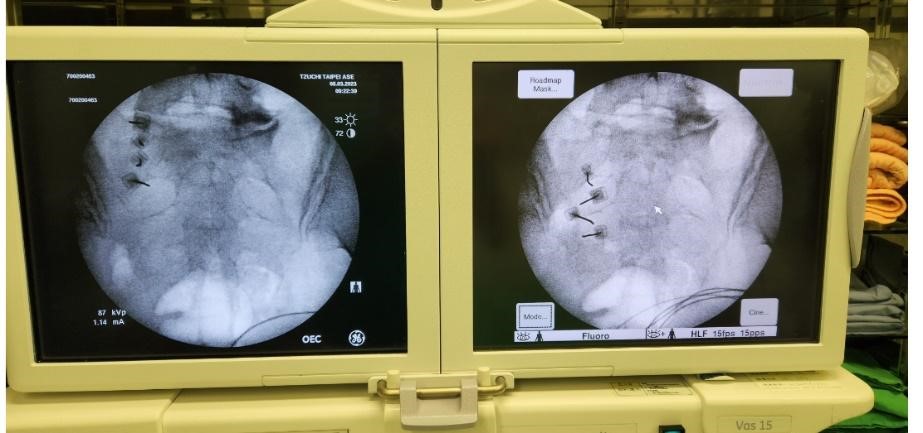

脊髓損傷的病人常因關節及脊椎的疼痛,影響到功能以及生活品質。射頻灼燒術(Radiofrequency ablation)是藉由影像導引,將治療探針(Needle Probe)置入支配關節的感覺神經做燒灼來達成止痛。